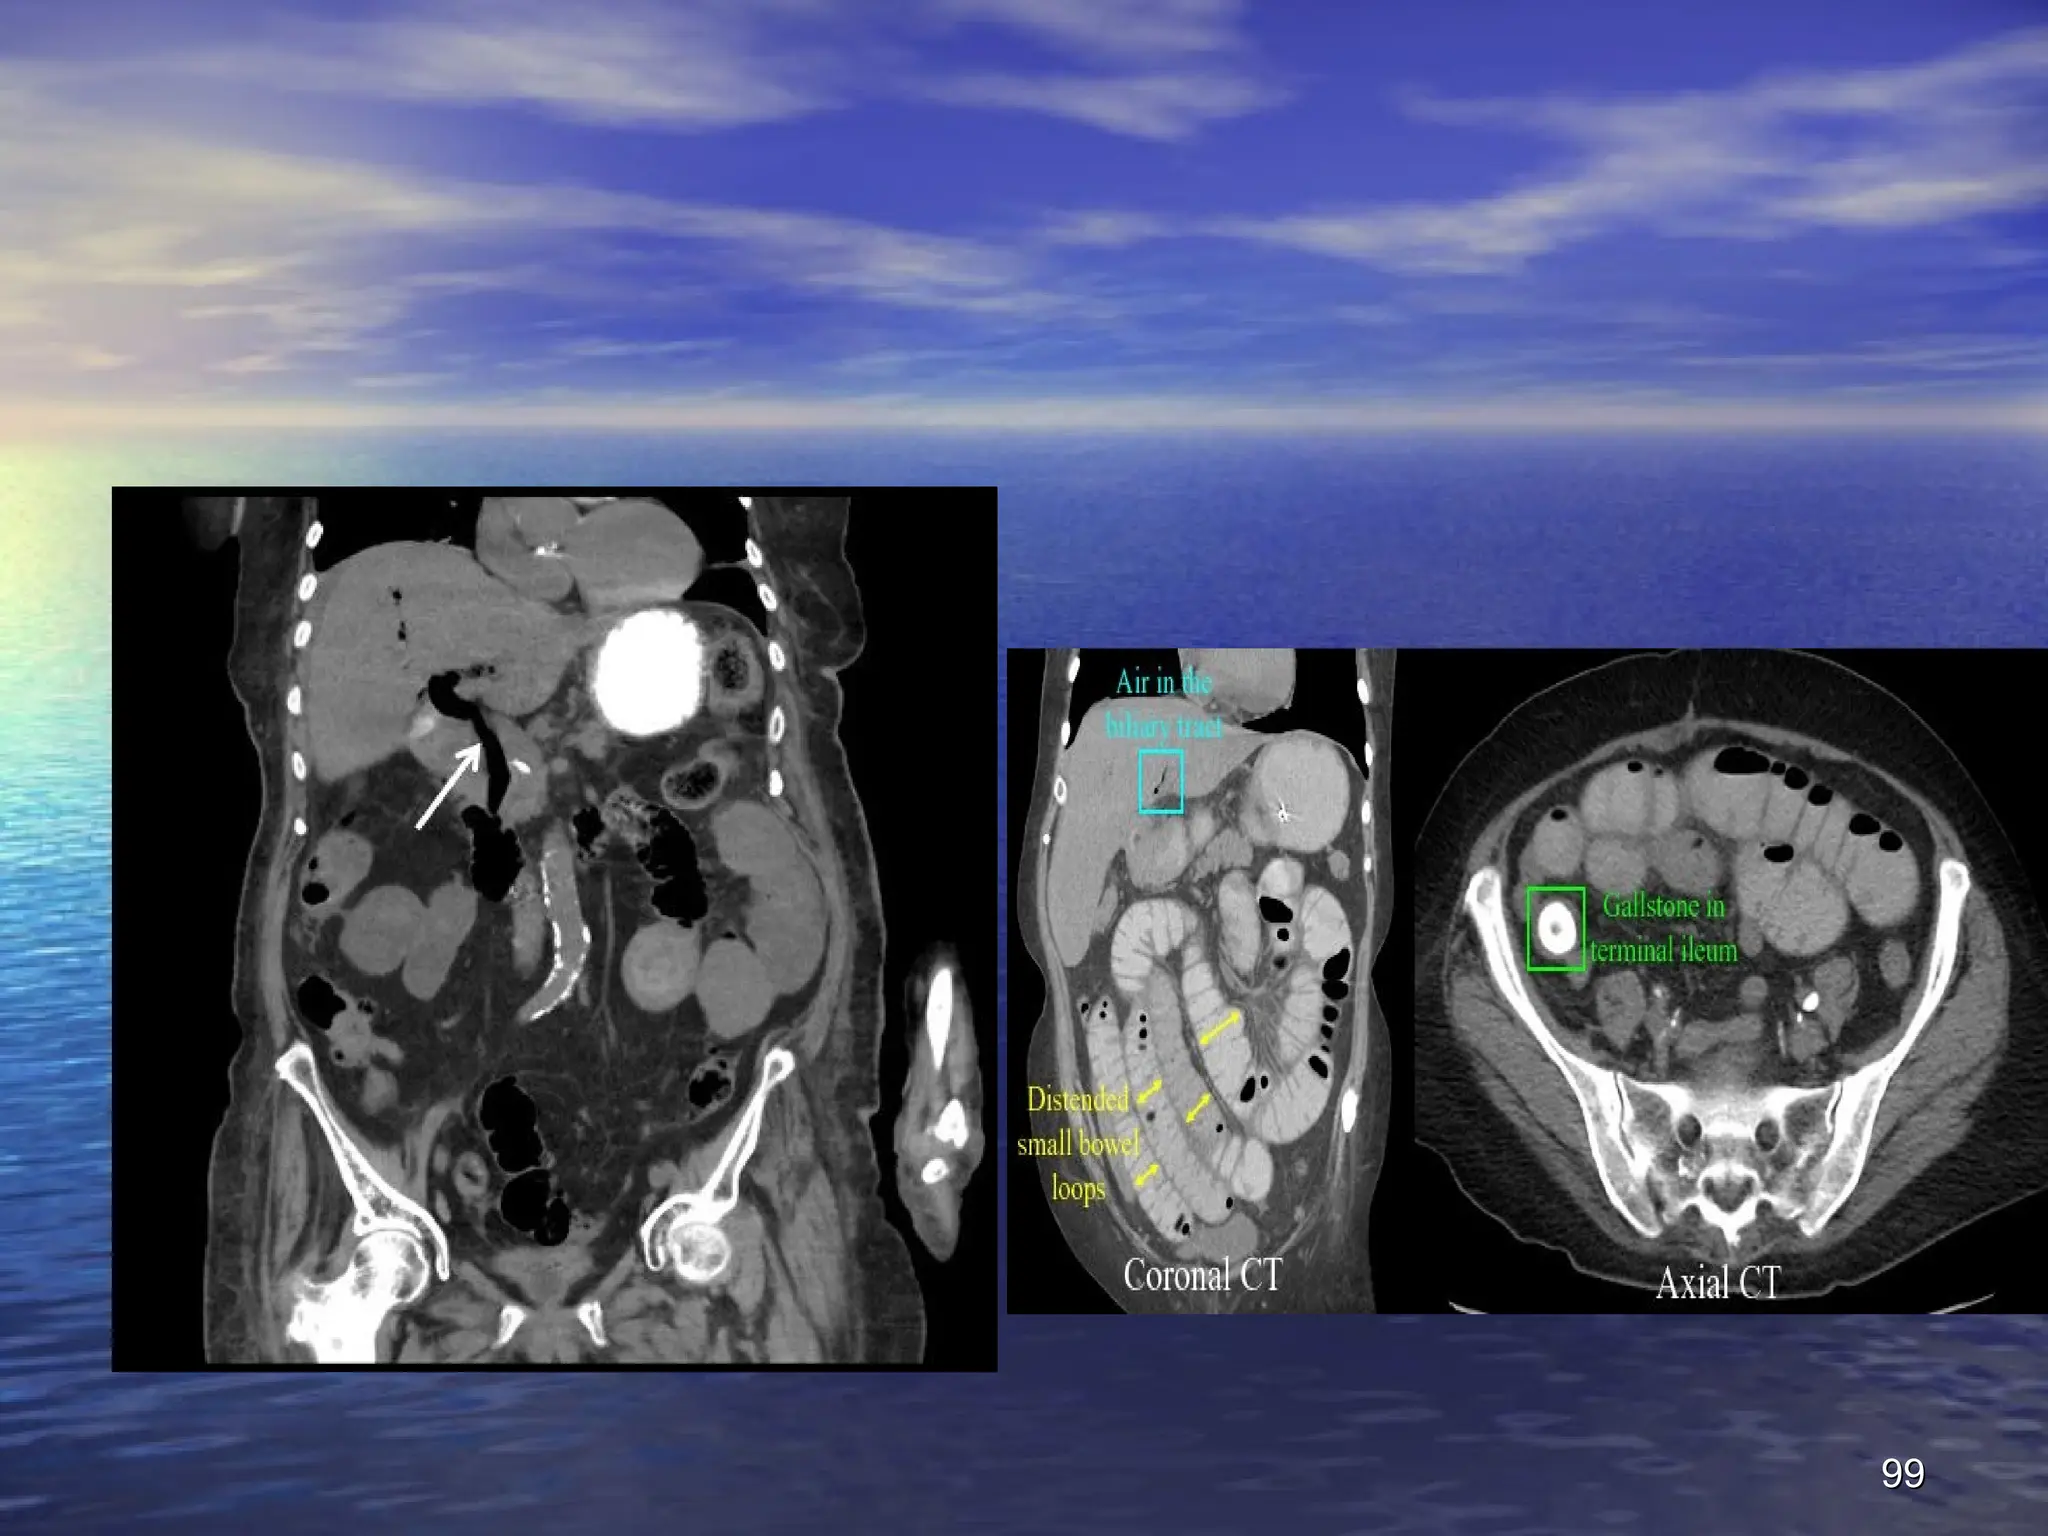

I. Gallstones: Gallstone Ileus (stones enter the

intestine through a fistulous communication

between the bile duct and the GI tract)

The characteristic radiological sign of gallstone ileus

is

Rigler's triad

:

small bowel obstruction

small bowel obstruction +

+ pneumobilia

pneumobilia +

+ atypical

atypical

mineral shadow on radiograp ectopic calcified

gallstone, usually in the right iliac fossa

Presence of two of these radiological signs has been

considered pathognomic of gallstone ileus

.